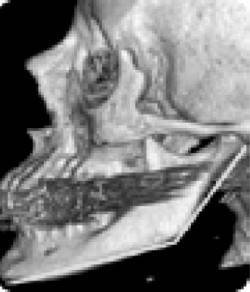

Еще одно сообщение Phys-Org: руководитель службы пластической и реконструктивной хирургии в американской университетской клинике Говард Лэнгстайн (Howard Langstein) на основании своих многочисленных исследований утверждает, что с возрастом происходит изменение угла нижней челюсти (показанные желтым цветом), длина и высота самого тела челюсти (рис. 10).

Рис. 10. Череп молодого человека

Рис. 10а. Череп старого человека

А поскольку нижняя челюсть является основной костью лицевой части лица, любые ее изменения влияют на общий вид лица.

Внешне это проявляется в том, что его нижняя часть приобретает более вялые очертания, мягкие ткани провисают, овал теряет свою четкость, снижается тонус кожи щек, подбородка и шеи, в результате чего очертания лица приобретают характерный возрастной вид. Далее Г. Лэнгстайн добавил: «Хотя врачи всегда знали, что кости со временем меняются, но как это проявляется с возрастом – не смогли оценить до конца».